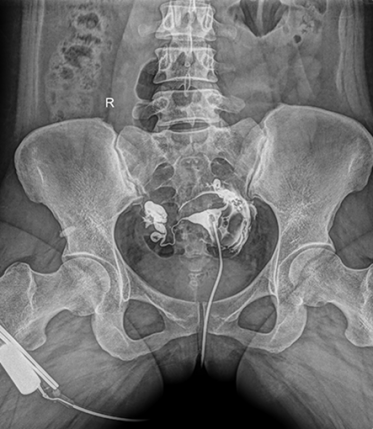

多功能動態(tài)平板DR,采用U型臂結(jié)構(gòu),具有靜態(tài)DR攝影、數(shù)字透視、數(shù)字造影和可視化攝影的功能。